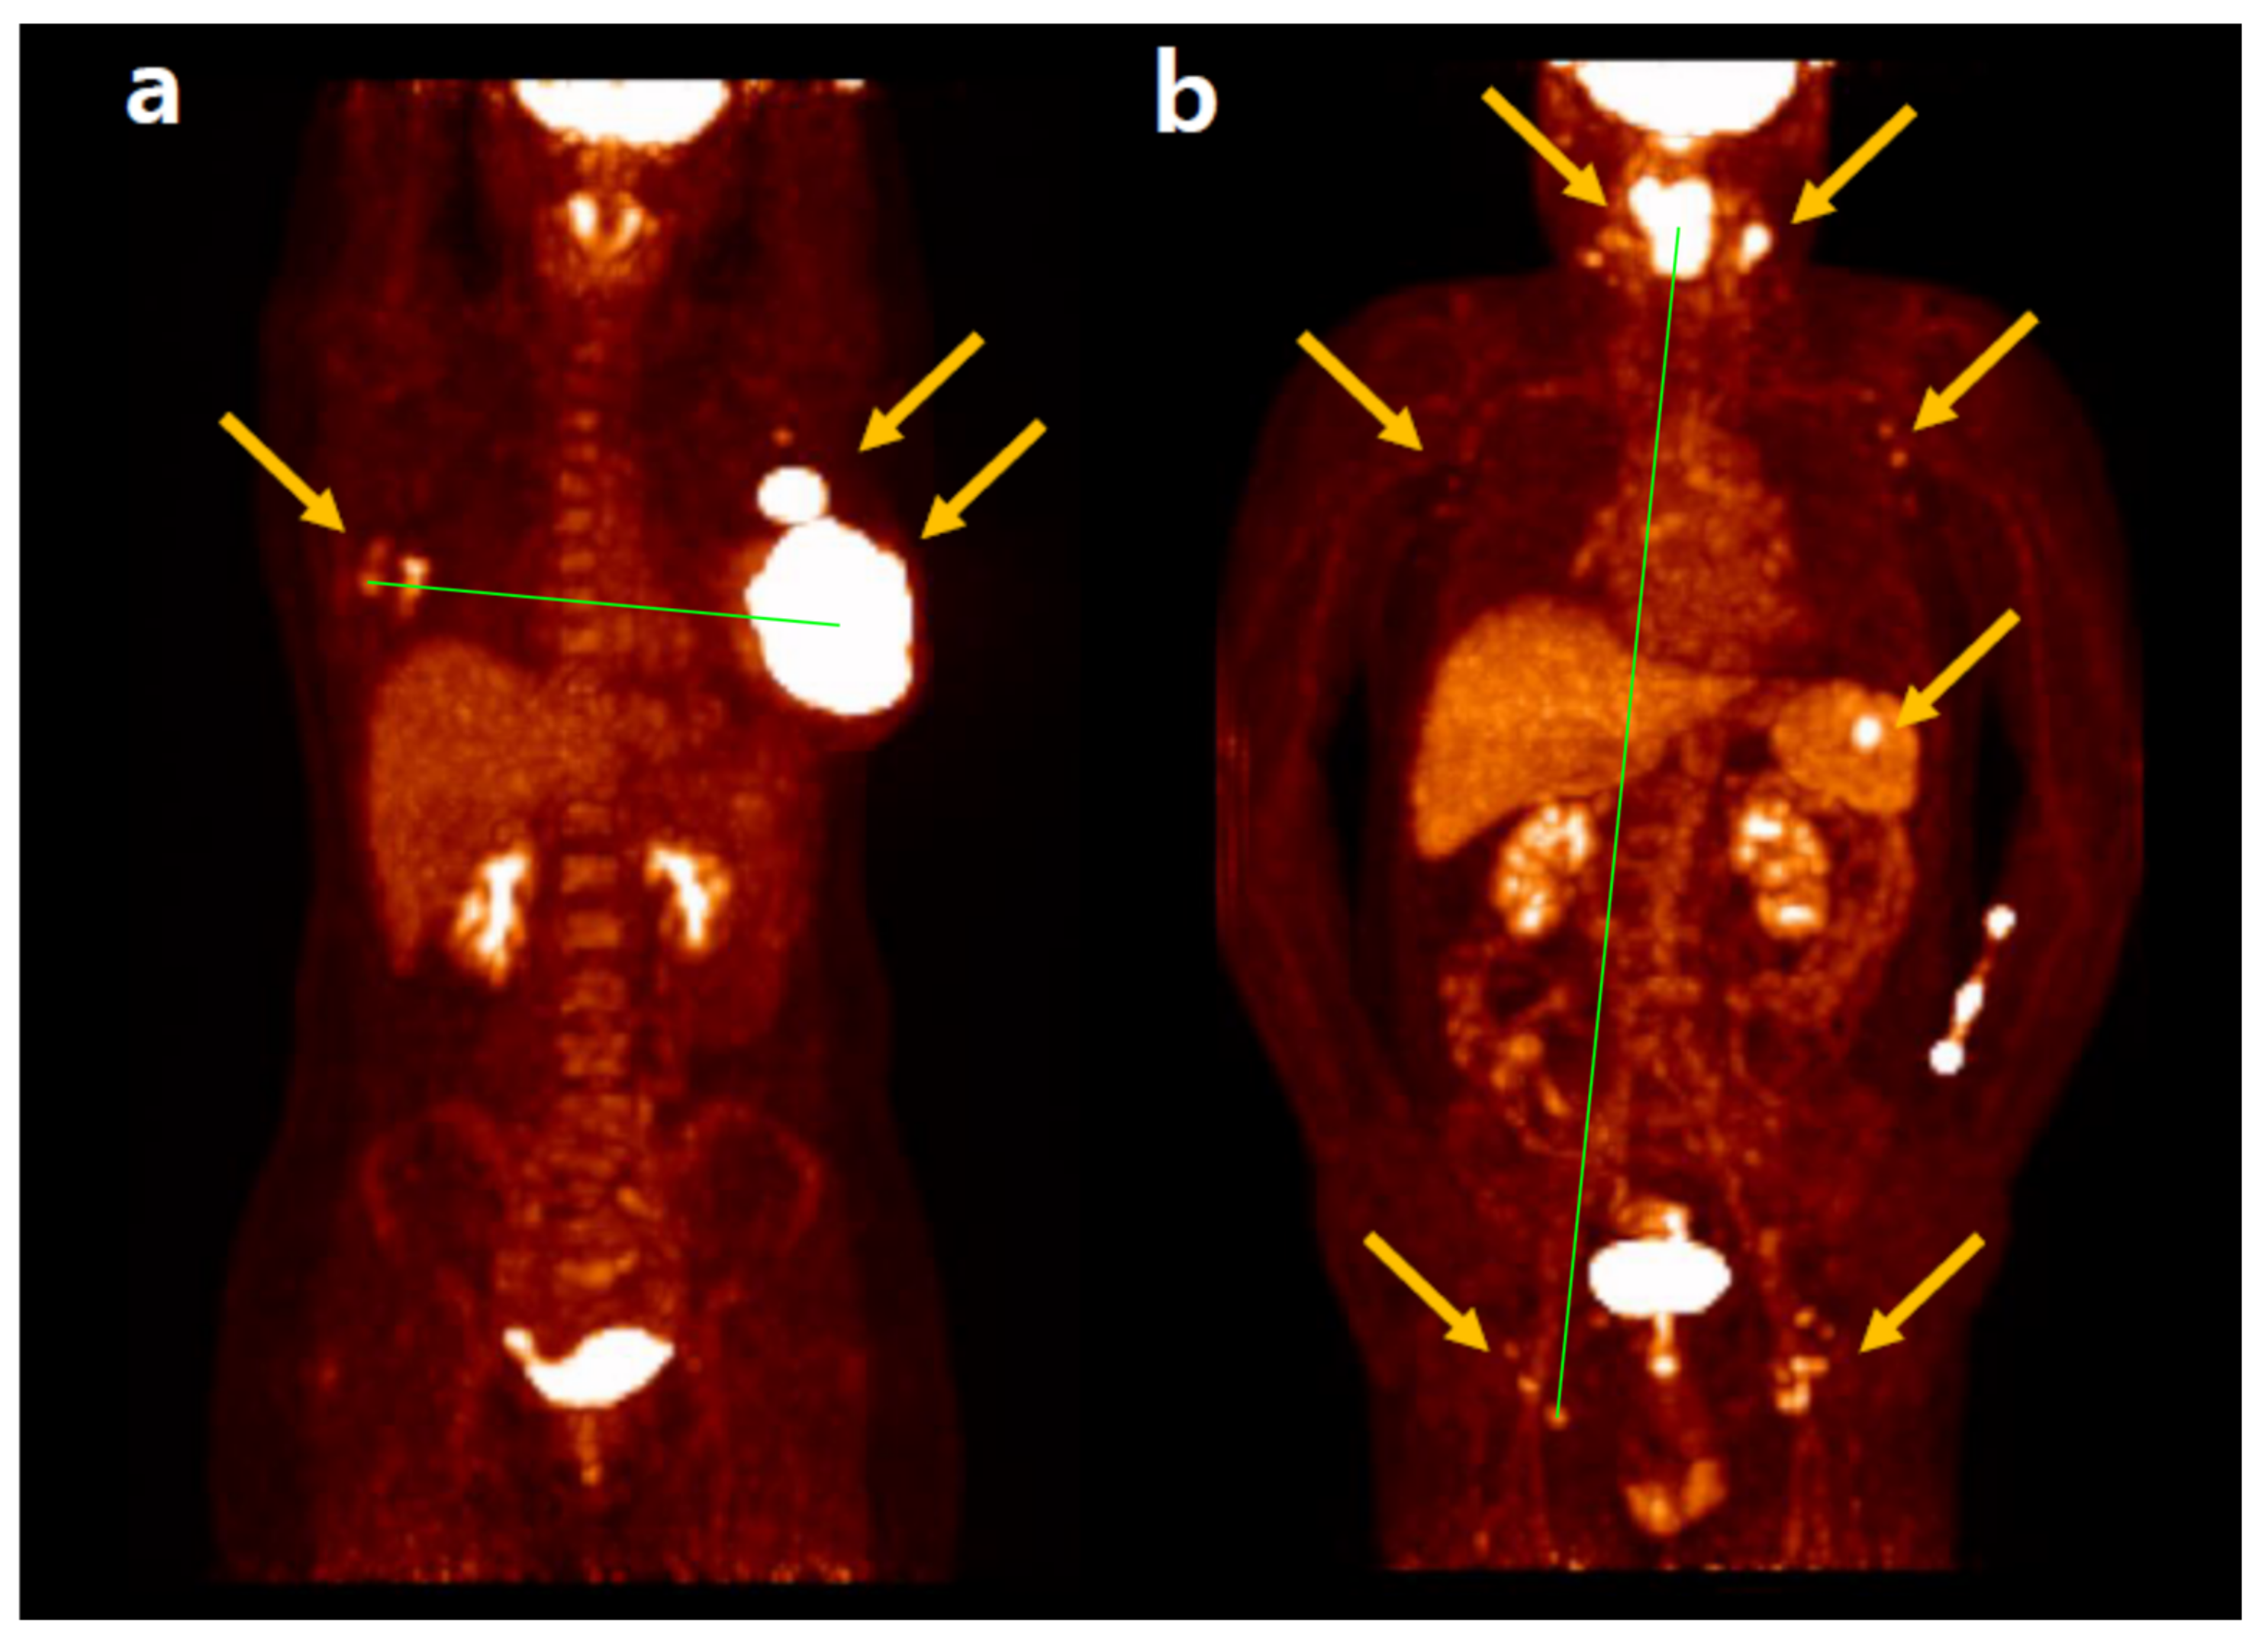

- Cottereau, A.S.; Meignan, M.; Nioche, C.; Clerc, J.; Chartier, L.; Vercellino, L.; Casasnovas, O.; Thieblemont, C.; Buvat, I. New Approaches in Characterization of Lesions Dissemination in DLBCL Patients on Baseline PET/CT. Cancers 2021, 13, 3998. [Google Scholar] [CrossRef] [PubMed]

- Albano, D.; Treglia, G.; Dondi, F.; Calabrò, A.; Rizzo, A.; Annunziata, S.; Guerra, L.; Morbelli, S.; Tucci, A.; Bertagna, F. 18F-FDG PET/CT Maximum Tumor Dissemination (Dmax) in Lymphoma: A New Prognostic Factor? Cancers 2023, 15, 2494. [Google Scholar] [CrossRef]

- Cottereau, A.S.; Meignan, M.; Nioche, C.; Capobianco, N.; Clerc, J.; Chartier, L.; Vercellino, L.; Casasnovas, O.; Thieblemont, C.; Buvat, I. Risk stratification in diffuse large B-cell lymphoma using lesion dissemination and metabolic tumor burden calculated from baseline PET/CT. Ann. Oncol. 2021, 32, 404–411. [Google Scholar] [CrossRef]

- Jo, J.H.; Chung, H.W.; Kim, S.Y.; Lee, M.H.; So, Y. FDG PET/CT Maximum Tumor Dissemination to Predict Recurrence in Patients with Diffuse Large B-Cell Lymphoma. Nucl. Med. Mol. Imaging 2023, 57, 26–33. [Google Scholar] [CrossRef]